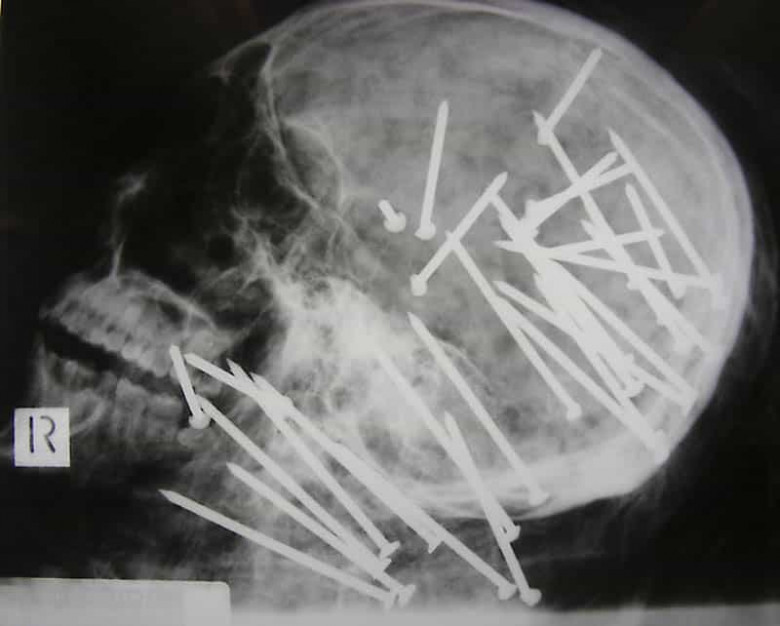

1. Չինացու գանգ, ում գլխին կրակել են պնևմատիկ մուրճից